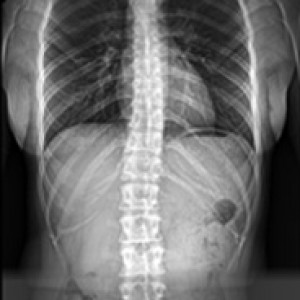

발의 아치가 무너지거나 발목 관절이 틀어지면 연쇄적으로 척추, 골반 불균형과 다리 길이 차이를 유발할 수 있습니다. 연산당당 족부 교정 장치는 이러한 전신의 구조 문제를 개선하기 위해 발의 아치와 발목 관절을 제자리로 교정합니다.

올바른 체형 개선

척추/관절 손상 방지

다리길이 측정

엑스레이 검사